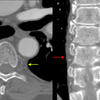

coronal CT

Date: 01/10/2010

Views: 7129